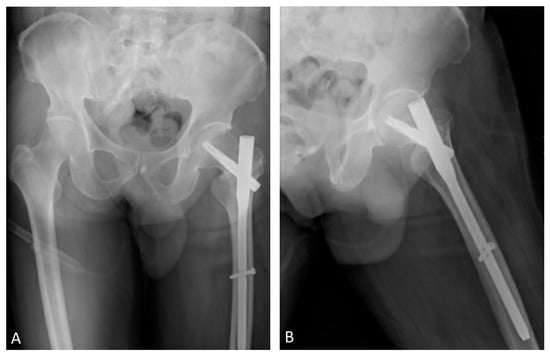

2. Case Report